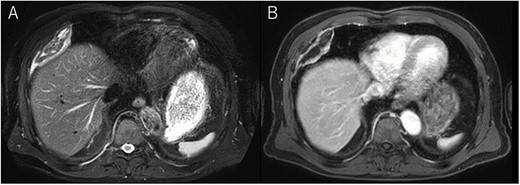

A 72-year-old man with a history of hypertension and left renal cancer (Stage I) was referred to us with a mass in the right chest wall on post-operative follow-up chest computed tomography (CT) for renal cancer. He had a smoking history of 20 pack-years and had no exposure to environmental fumes or dust. Physical examination results were unremarkable. The laboratory findings were within normal limits. Pulmonary function tests and cardiovascular examinations revealed normal results. Chest CT revealed mixed density mass (8.0 × 5.0 × 3.0 cm) located in front of thoracic wall in the third to sixth right intercostal space. The tumor can be revealed as thoracic wall fat (7.8 × 4.8 × 1.2 cm) on CT 1 year before (not considered as abnormal), and it was progressively increased in size and the density changed (Fig. 1A and B). Magnetic resonance imaging (MRI) showed a fatty mass of heterogenic density. T2 high foci (Fig. 2A) and irregular marginal enhancement of the tumor were observed (Fig. 2B). Maximal standard uptake value (SUVmax) of 18F-fluorodeoxyglucose positron emission tomography (FDG-PET) was 3.78 (Fig. 3). Based on these radiological image findings, we scheduled surgery with suspicion of liposarcoma. During the surgery, the patient was placed in the lateral decubitus position. We made 1.5-cm incision in the sixth intercostal space along the posterior axial line for thoracoscopy. We found dense adhesions between the chest wall tumor, lung (front part of all three lobes of the right lung) and diaphragm. We made a 30-cm incision in the fourth intercostal space and resected the tumor along with lung (wedge resection of the front part of all three lobes of the right lung), diaphragm and third to sixth ribs and intercostal muscle. The chest wall defect was 25 × 15 cm and the diaphragm defect was 8 × 5 cm. For reconstruction, the mesh was placed and sutured to the diaphragm and the chest wall. Pathological examination revealed the well-circumscribed tumor with fibrous adhesion between the ribs, lung and diaphragm (Fig. 4A). Microscopically, the tumor consisted of mature fat tissue. There were fat necrosis inflammatory changes in the marginal area of the tumor with foamy macrophages and multinucleated giant cells (Fig. 4B and C). Fluorescence in situ hybridization examination for murine double-minute 2 was negative. Based on these findings, a chest wall lipoma was diagnosed. The post-operative course was uneventful. The patient was followed up for 24 months without evidence of recurrence.

Chest MRI; (A) T2-weighted imaging showed several high signal foci in the tumor; (B) irregular marginal enhancement was observed.